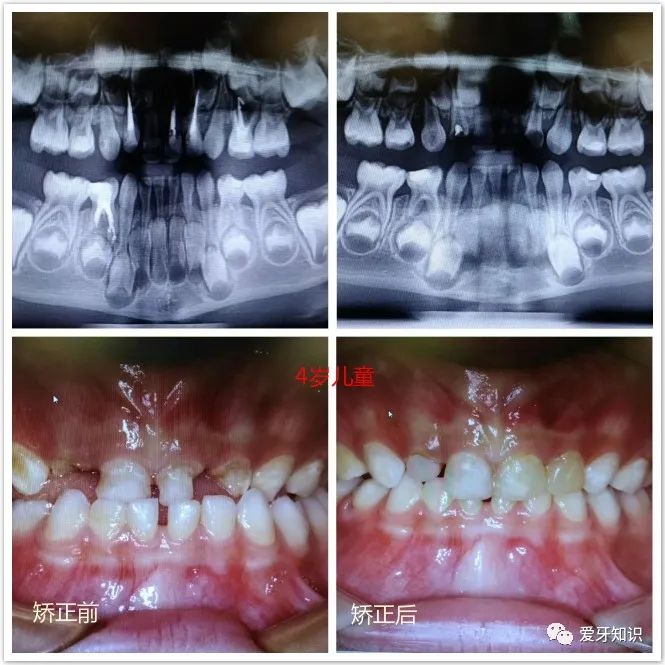

5岁儿童地包天早期矫正效果。

4岁儿童早期矫正地包天前后效果。